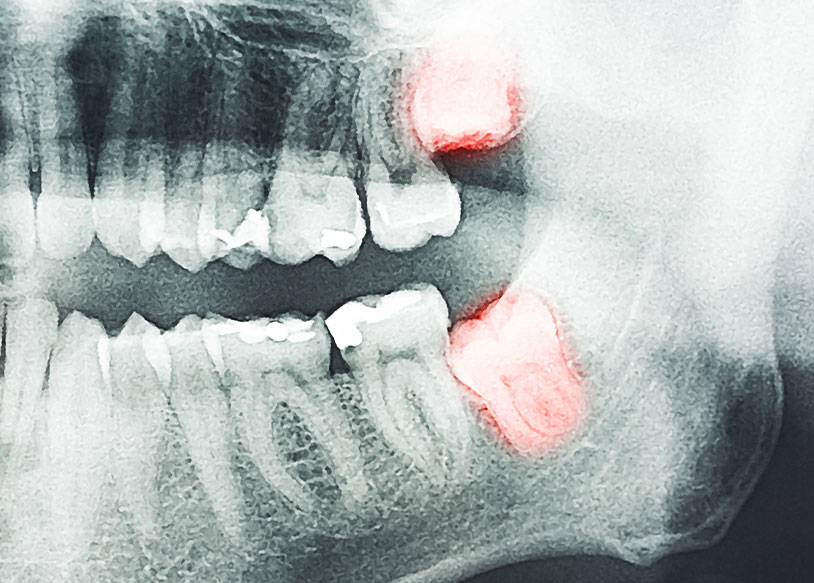

親知らずは20歳前後に生えてくる場合が多く、正しく生えずに歯ぐきの中で横になってしまう場合もあります。

また、親しらずは生えるスペースが少ないため、歯ブラシが届きにくいので虫歯になりやすいですし、右下、左下の顎で横向きに生えている場合、手前(隣)の臼歯をおして歯列を悪くしたり、むし歯にさせてしまう場合もあるため、親知らずは抜歯をすすめられることが多い歯です。

ただし、歯は上下で噛み合っていないと歯の役割を果たしませんし、真っ直ぐ生えることも少なく、横向きに倒れて生えることもあり、汚れが残りやすいことから歯周組織が炎症を起こして歯肉(歯ぐき)が腫れて膿んでしまう原因にもなりやすい歯です。

親知らずが、真横に埋まっている場合などは、抜歯治療をしてもらったほうが安全です。